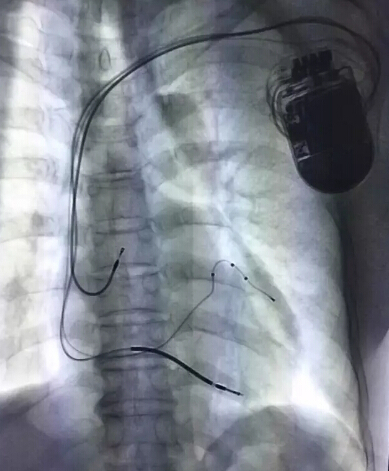

当天远程监护管理中心启动仪式结束后,心血管内科谢鸿发教授及姚启恒教授成功为一名中年女性患者植入左室多位点起搏(MPP)心脏再同步复律除颤器(CRT-D)。

这名57岁女性患者诊断为扩张型心肌病心功能不全NYHA IV级,左室射血分数仅30%,同时合并了室速、室颤、窦性停搏等恶性心律失常,需要植入带起搏功能的ICD。但植入ICD后预期会加重心衰,适合植入CRT-D。经前期充分准备,谢教授手术团队顺利植入MPP CRT-D。

传统的CRT-D左室电极仅为双极,存在术中和术后起搏阈值高、膈神经刺激、电极易脱位、起搏部位不佳、部分患者无反应等难题。MPPCRT-D以四极左室电极多部位起搏为最大特点,解决了以上诸多弊端,让心衰患者最大程度获益,是治疗心衰的里程碑式的进步。此例手术在深圳市尚属首例,广东省范围内的第二例。完成这一植入手术,标志着我院心血管内科CRT-D治疗达到国内领先水平。

CRT-D治疗的难点在于左室电极的植入及术后CRT反应率问题(研究表明,43%患者在植入CRT六个月后,在LVESV评估中属于无反应或负反应)。左室四极导线的运用提高了心脏再同步化治疗手术成功率,降低手术并发症发生几率。通过同一条左室电极导线发放两个起搏脉冲(LV1-LV2),为心衰心衰患者提供上千种起搏顺序和起搏间期参数组合。在此基础上,多项临床研究证明MPP左室多位点起搏能够进一步改善患者的CRT反应率。

与传统双室起搏相比,MPP左室多位点起搏可提高机械同步性,改善急性血流动力学,提高CRT反应率达19%。最新研究证据证明,CRT优化联合MPP治疗在ESV减少≥15%的标准、NYHA分级降低≥1级的标准、PACKER评分变异(无心衰相关住院或者死亡)的标准评估中都优于传统BiV CRT治疗及CRT优化治疗。